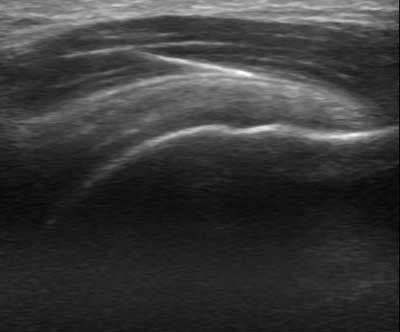

La técnica EPI® consiste en un primer lugar en realizar una recogida de datos del deportista e historia de su lesión, mediante ecografía músculo-esquelética se realizará un estudio para ver el origen de la lesión, diferenciando ensopatías, tendinopatias, fibrosis y roturas musculares. Creando un protocolo personal con diferentes técnicas y ejercicios dirigidos por un Fisioterapeuta . En muchas ocasiones el ejercicio debe ser corregido mediante vendaje, tipo MaCconnell para la corrección de la alineación rotuliana, y aminorar el dolor.

La aplicación de la técnica EPI, consistirá pues en una aplicación de un tipo concreto de electroterapia Galvánica continua con un aguja mediante control eco-guiado para producir una respuesta inflamatoria del tejido degenerado e inducir a su proceso de reparación fisiológico, favoreciendo así la reparación del tejido blando afectado. Ya en 1996, Balcavage et al. observaron que la corriente eléctrica inducida en el tejido a frecuencias bajas (50-60 Hz) tiene un efecto directo sobre la membrana celular.